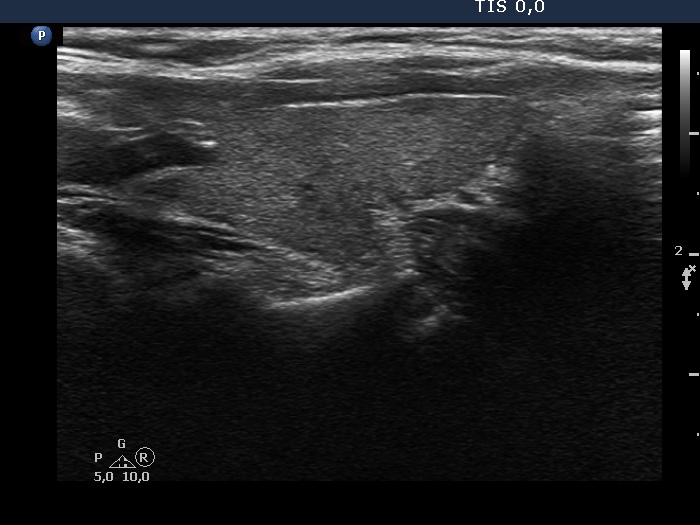

The echogenicity of the nodule - case 2071

Examination 28 months later (ultrasonographic picture 5)

Left lobe, longitudinal scan.